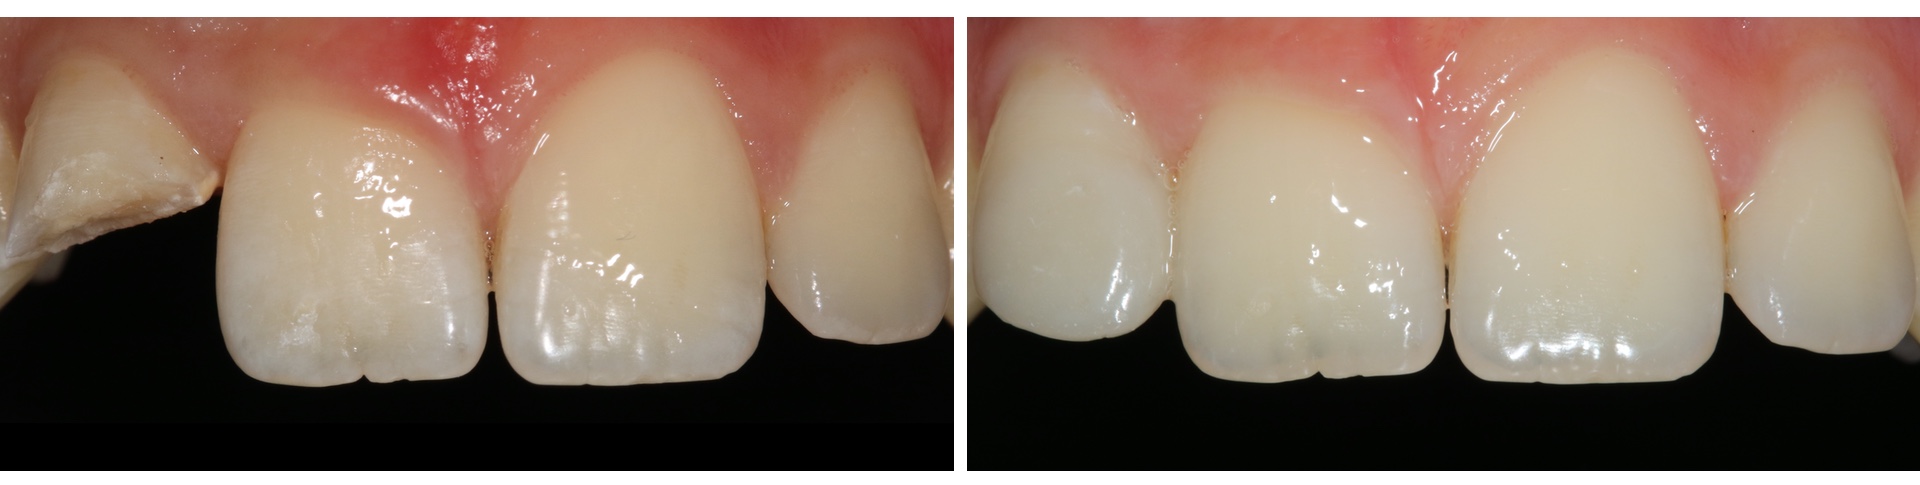

Olyan kifejezetten esztétikai célzatú beavatkozás, mely alkalmazásával megváltoztathatja a fogak formáját, színét csiszolás nélkül, vagy mindössze minimális foganyag eltávolításával. Az eljárás alkalmas kisebb helyzeti rendellenességek, illetve rések korrekciójára.